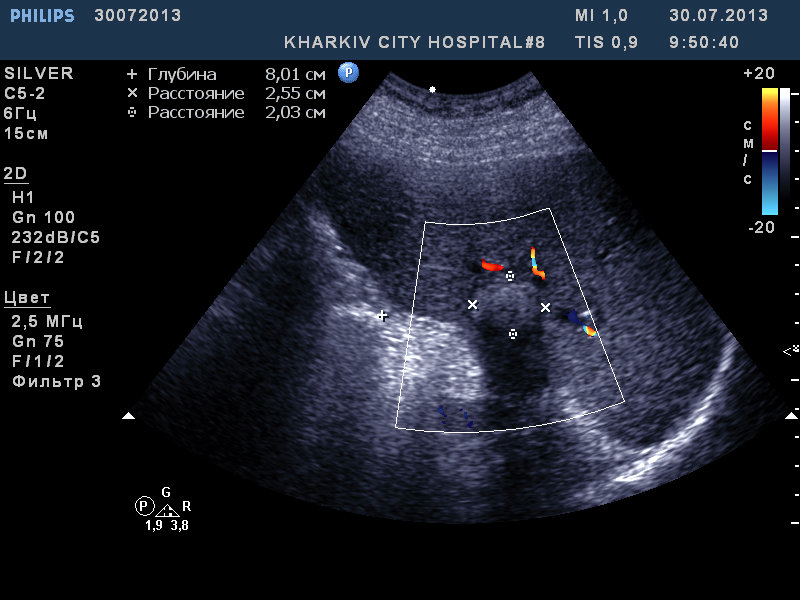

Амбулаторный пациент с тяжелым аортальным стенозом. увидел два образования печени: гиперэхогенное (гемангиома?) и гипперэхогенное кальцинирующей плотности. Рекомендовал КТ.

13-07-30.jpg